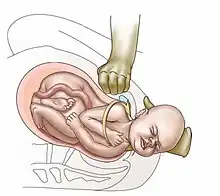

| Suprapubic pressure being used in a shoulder dystocia | |

Shoulder dystocia is when, after vaginal delivery of the head, the baby's anterior shoulder gets caught above the mother's pubic bone.[3][1] Signs include retraction of the baby's head back into the vagina, known as "turtle sign".[1] Complications for the baby may include brachial plexus injury, or clavicle fracture.[2][1] Complications for the mother may include vaginal or perineal tears, postpartum bleeding, or uterine rupture.[3][1]

Shoulder dystocia is an obstetric emergency.[3] Initial efforts to release a shoulder typically include: with a woman on her back pushing the legs outward and upward, pushing on the abdomen above the pubic bone.[3] If these are not effective, efforts to manually rotate the baby's shoulders or placing the woman on all fours may be tried.[3][2] Shoulder dystocia occurs in approximately 0.4% to 1.4% of vaginal births.[2] Death as a result of shoulder dystocia is very uncommon.[1]

- Anterior shoulder disimpaction (suprapubic pressure);[11]